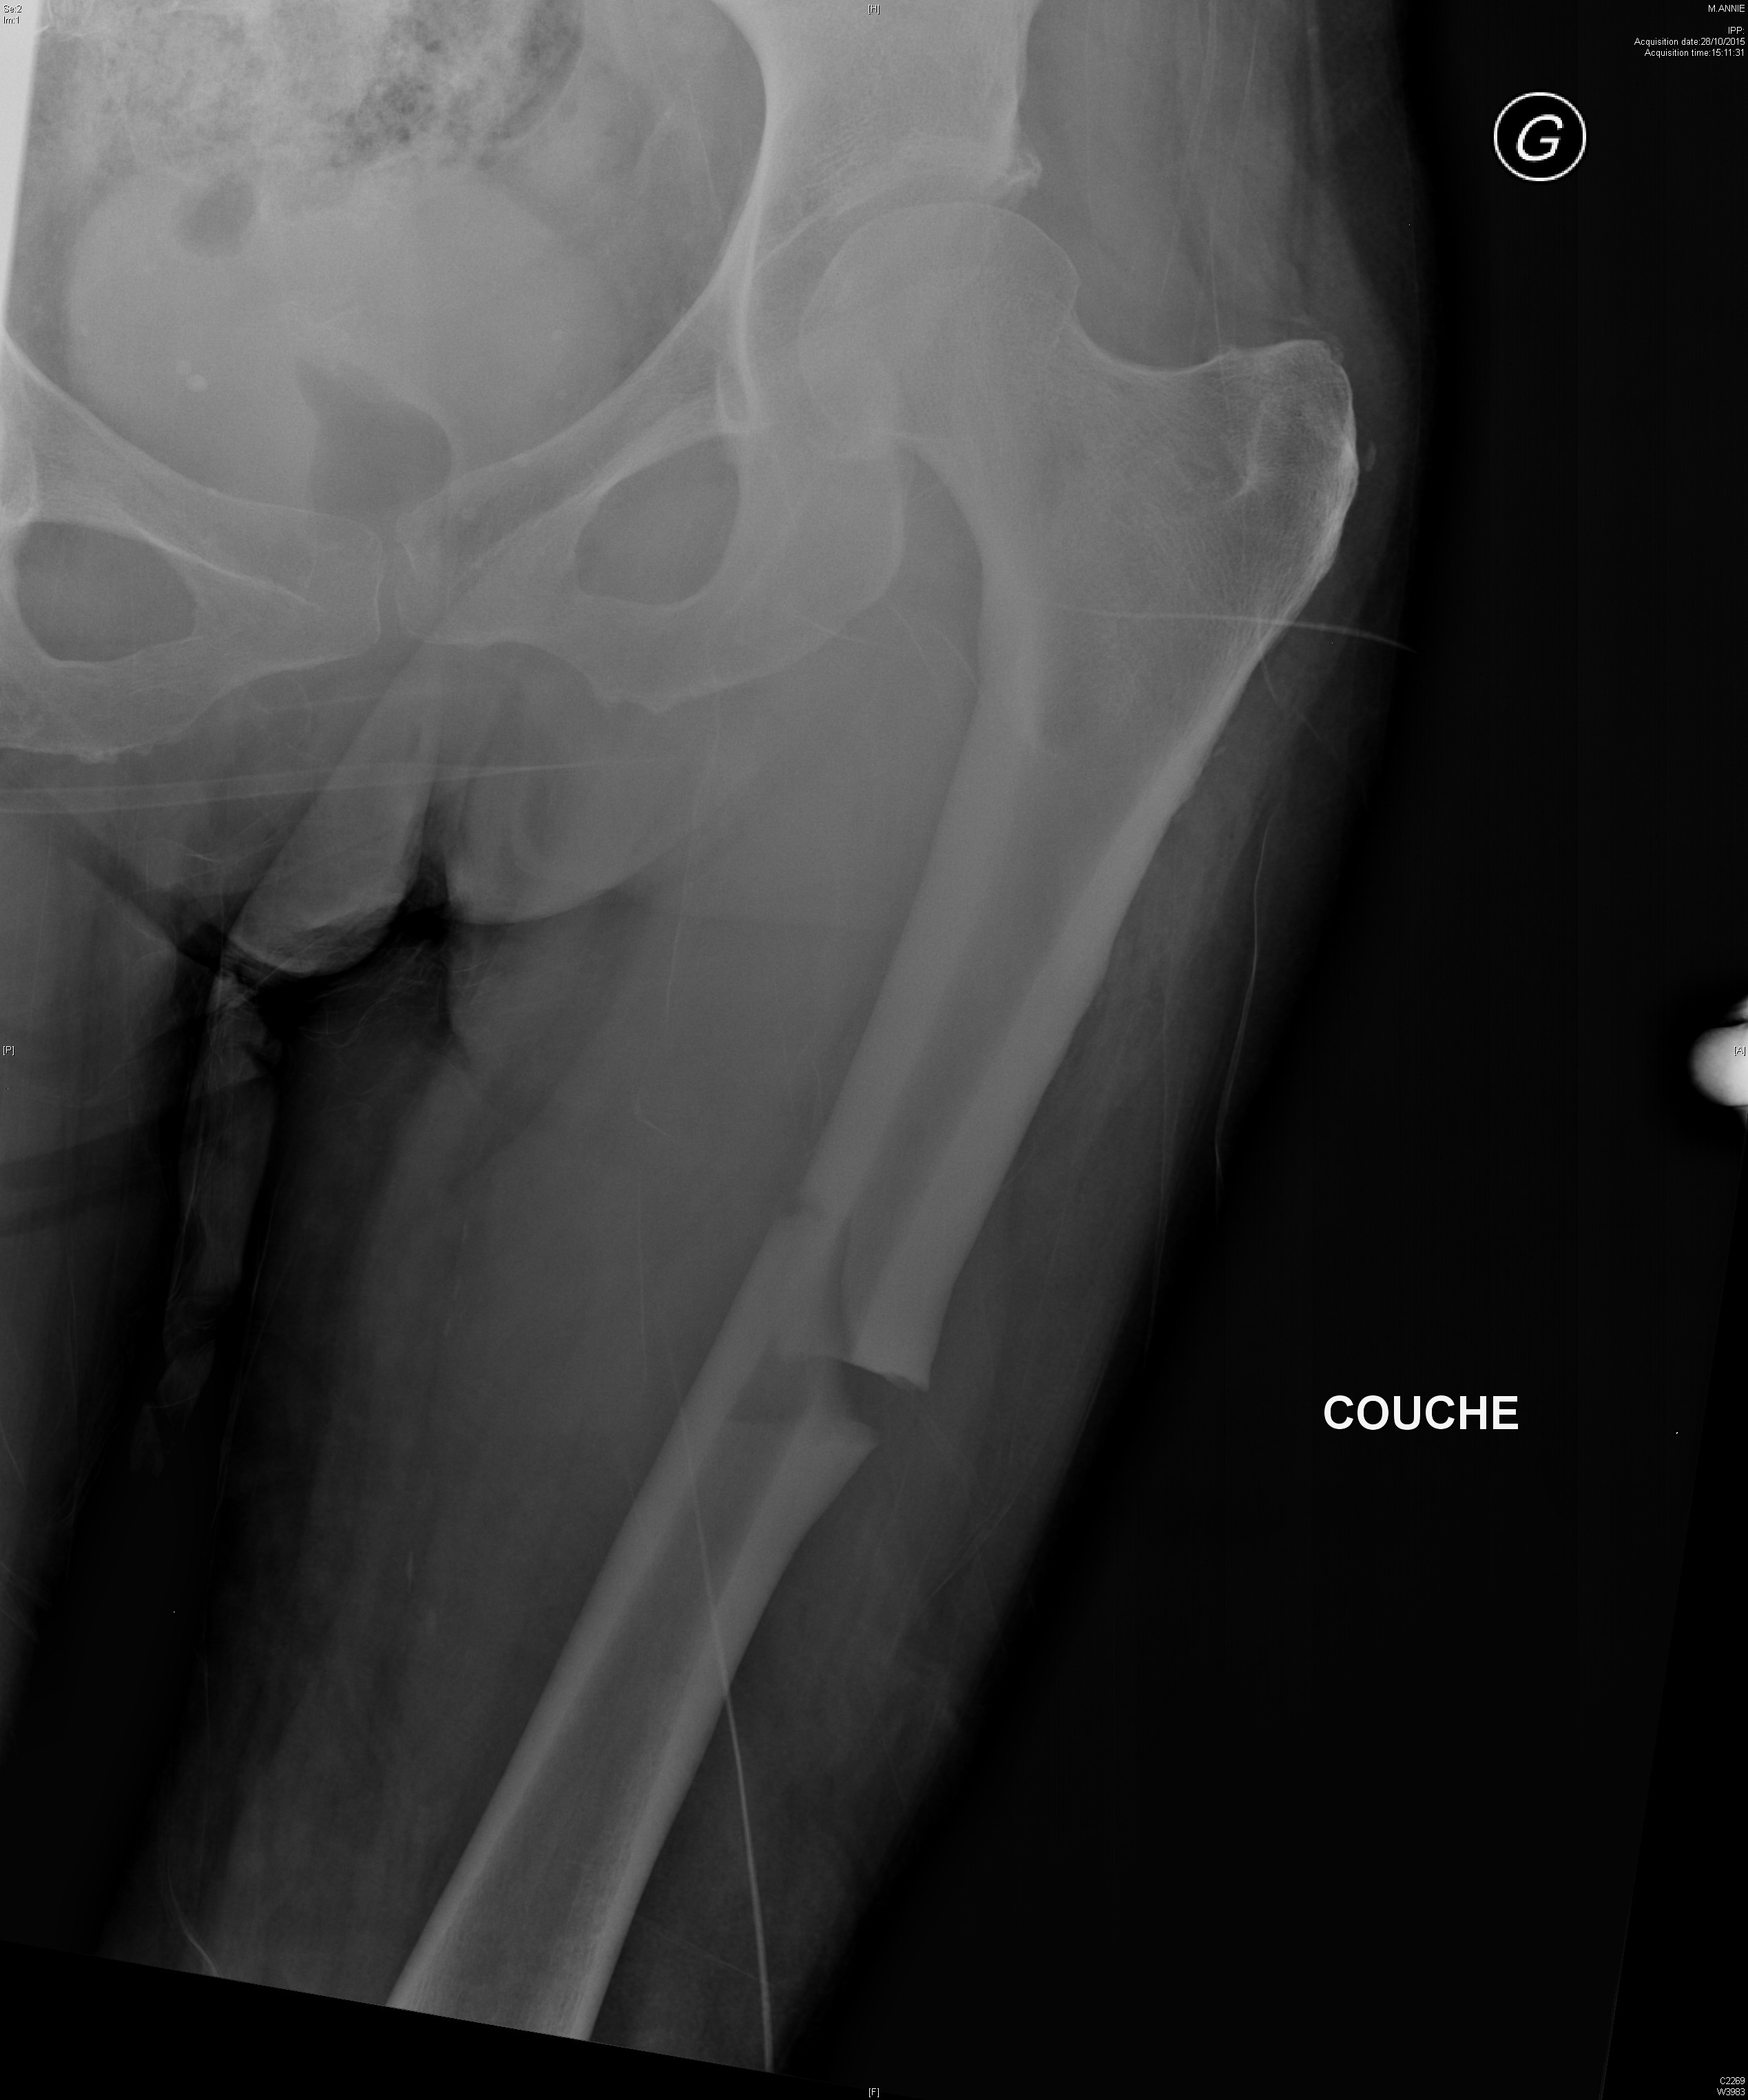

Dysplasie fibreuse du fémur gauche dans un contexte de dysplasie fibreuse polyostotique